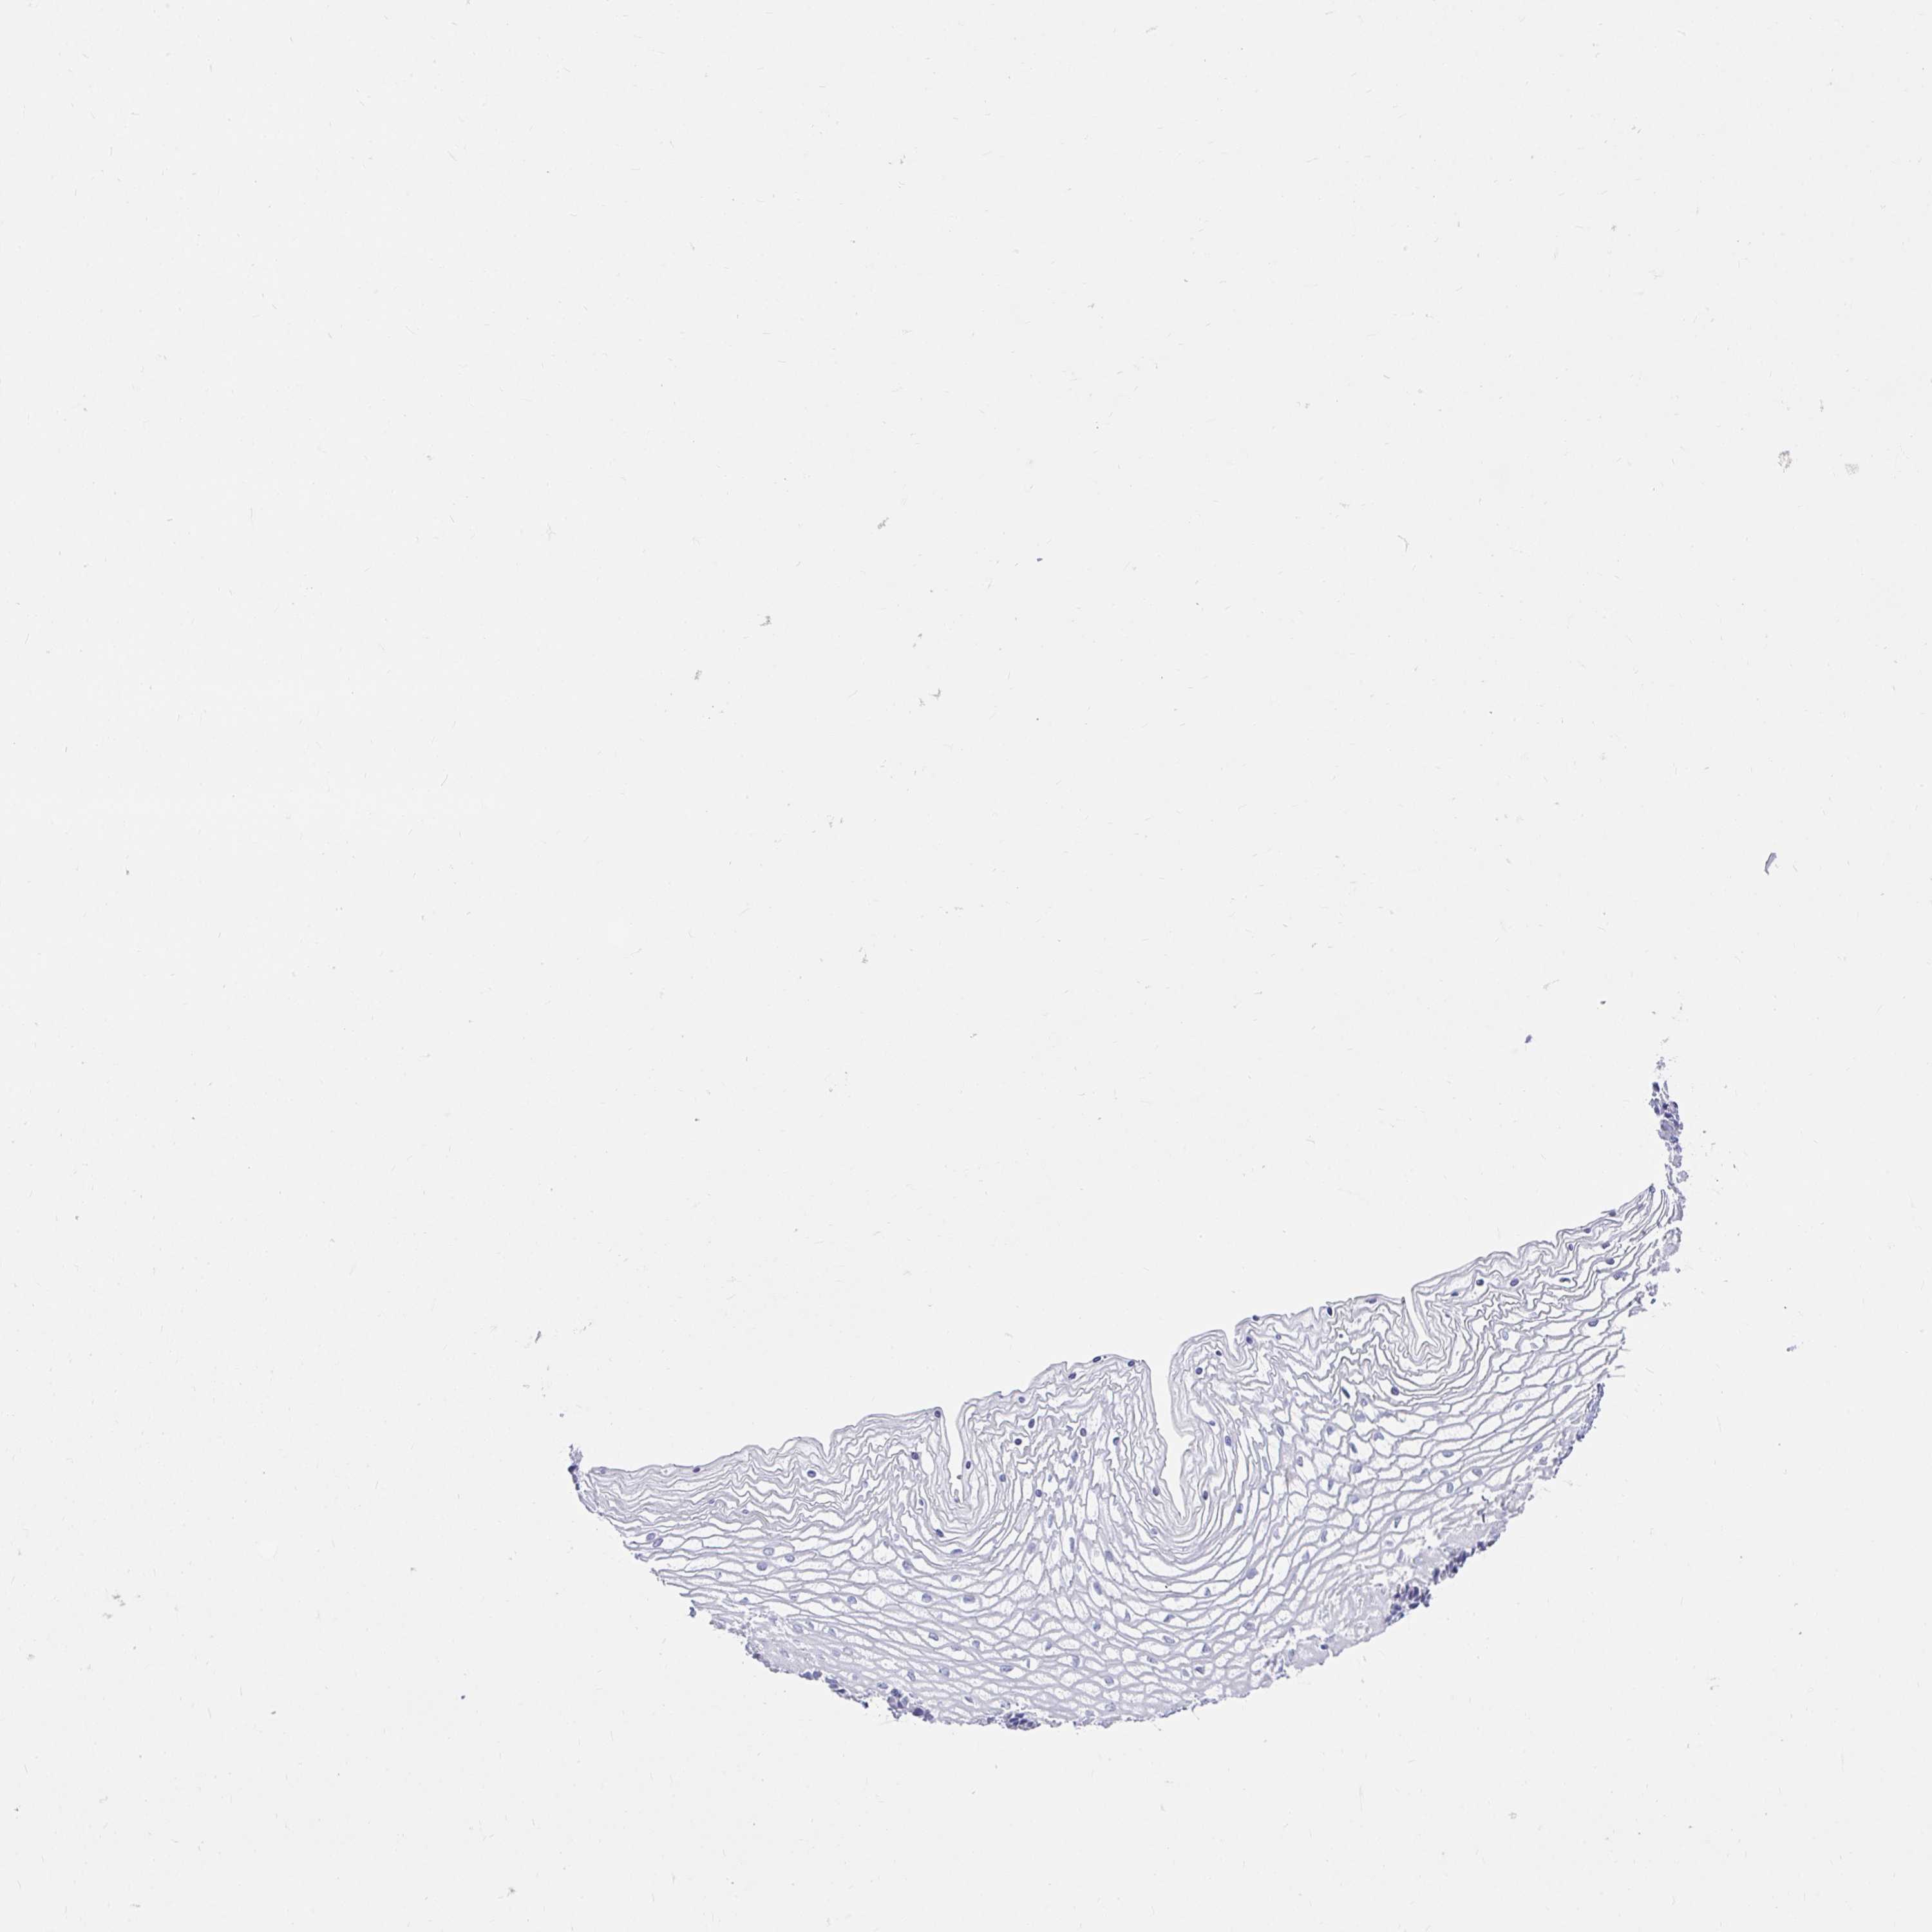

VAGINA - Antibody stainingi

Antibody staining in the annotated cell types in the current human tissue is reported as not detected, low, medium, or high, based on conventional immunohistochemistry profiling in selected tissues. This score is based on the combination of the staining intensity and fraction of stained cells.

Each image is clickable and will lead to virtual microscopy that enables deeper exploration of all samples and also displays staining intensity scores, fraction scores and subcellular localization as well as patient and tissue information for each sample.

Antibody HPA042403

Squamous epithelial cells Not detected